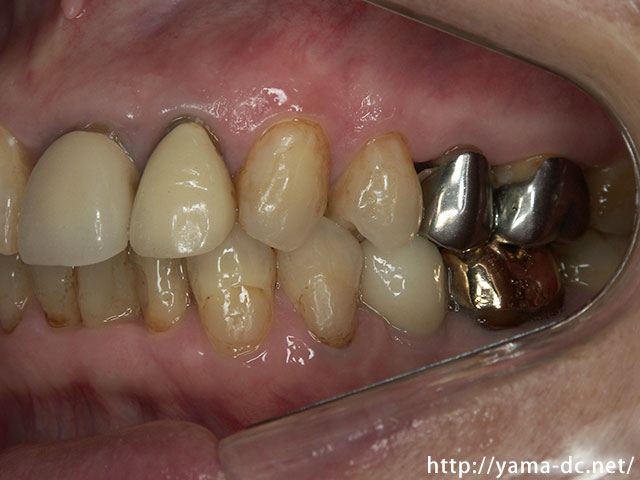

<従来法>

健康な歯に金属のバネをかけて入れ歯を固定します。違和感があり、バネをかけた歯にも負担がかかります。

<インプラント>

入れ歯の床や金具の違和感がなく、バネをかけた健康な歯への負担もありません。